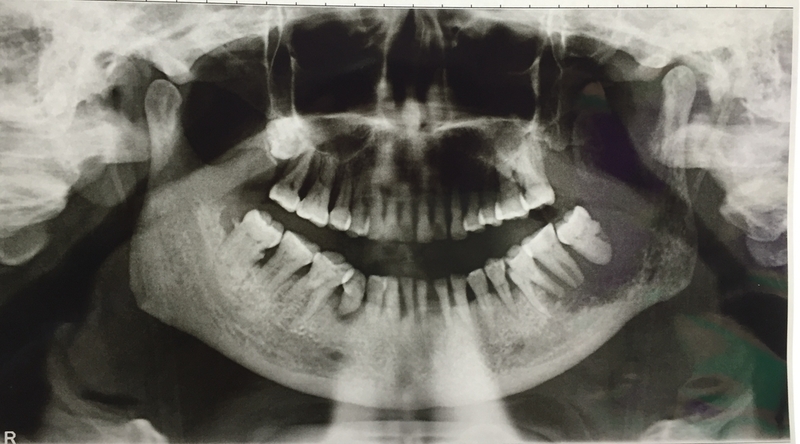

Oral cancer is considered one of the most predominant cancers found among men in Indian subcontinent. It is mostly caused by chewing of tobacco. The cancer is often diagnosed at advanced stages which results in poor survival rates among patients. Most of the oral cancer reported global are found in developing/underdeveloped regions including India where per capita consumption of tobacco is high. In spite of many therapeutic advancements, there has been no significant improvement in survival outcome of such cancer patients in the last decade.

In the new study, scientists of NIBMG have discovered five biomarkers which can make it possible to tell in advance if a person with oral cancer of the gums and cheeks has lymph node metastasis or not. The prediction is 80-90% accurate.